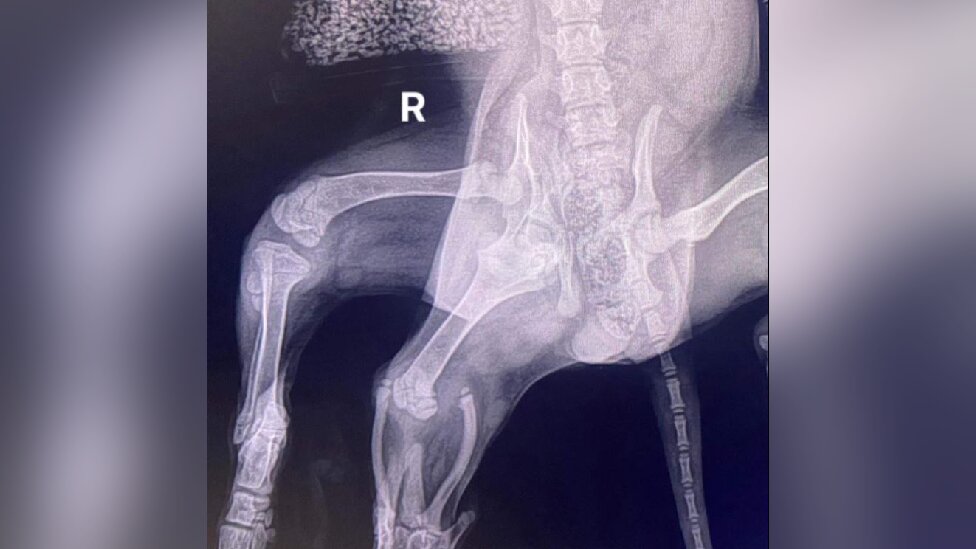

Arijel, keruša rođena sa šest nogu koju su ostavili na parkingu supermarketa, uspešno je operisana i uklonjena su joj dva suvišna ekstremiteta.

Hirurzi su uspeli da joj sačuvaju sve četiri „normalne“ noge, iako se strahovalo da će jedna od njih morati da bude uklonjena.

„Veterinar koji je obavio prvi pregled uočio je da, pored dve dodatne zadnje noge, Arijel ima i dve vagine“, kazao je 42-godišnji Lolor.

„Kako ima dva kuka na jednoj strani tela, njena karlica se nije razvila kako treba.

„Usled toga, njena regularna desna zadnja noga nije imala mišićni tonus, pa je postojala mogućnost da će i nju odstraniti.

„Srećom to se nije desilo, jer je noga značajno ojačala tokom prethodnih meseci“, objašnjava.